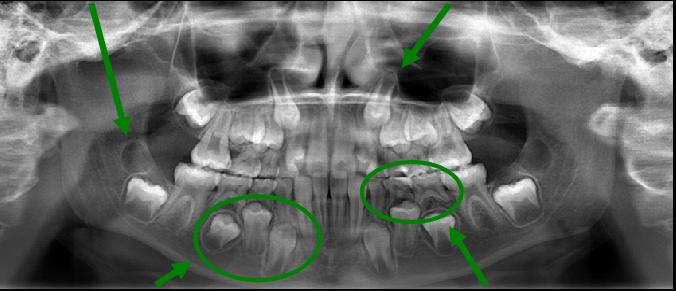

ภาพรังสีแพโนรามา

(ภาพรังสีปริทัศน์)

ภาพรังสีปริทัศน์เป็นการถ่ายภาพรวมที่ใช้ปริมาณรังสีเพียงเล็กน้อย เพื่อใช้ภาพแสดงทั่วทั้งบริเวณขากรรไกรบนและล่าง

สามารถแสดงให้เห็นโครงสร้างและรูปร่างของฟัน ปาก ช่องคอและบริเวณใกล้เคียงทั้งหมด

ภาพรังสีปริทัศน์มีความสำคัญเป็นพิเศษต่อการประเมินการเจริญพัฒนาของฟัน ซึ่งเป็นสิ่งที่สำคัญอย่างยิ่งต่อการรักษาทางทันตกรรมจัดฟัน จากภาพทำให้สามารถเห็นรูปร่างและตำแหน่งของหน่อฟันที่ยังไม่งอก ทำให้สามารถตรวจพบฟันซ้อนหรือหน่อฟันที่ขาดหายไปได้ และสามารถทำให้มองเห็นรากของฟันที่ยังมีอยู่

ทันตแพทย์จัดฟันสามารถวินิจฉัยได้จากรูปร่างของรากฟันว่า ฟันจะเคลื่อนที่ได้หรือไม่ หรือจะมีอุปสรรคในการเคลื่อนฟันทางทันตกรรมจัดฟัน

หลังจากทำการรักษาทางทันตกรรมจัดฟันเรียบร้อยแล้ว ภาพรังสีปริทัศน์ก็ยังมีความจำเป็นอย่างยิ่งในการกำหนดตำแหน่งของฟันกรามซี่ที่ 3